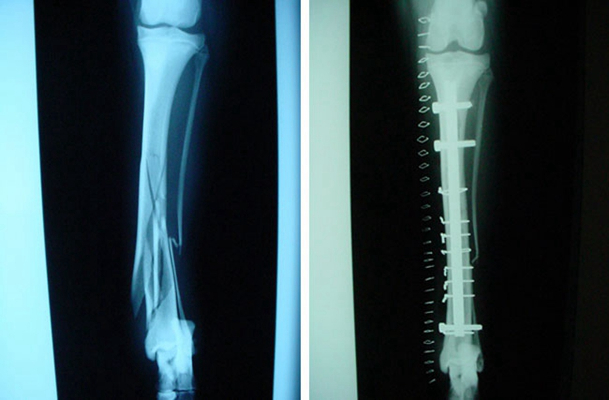

骨折圖片